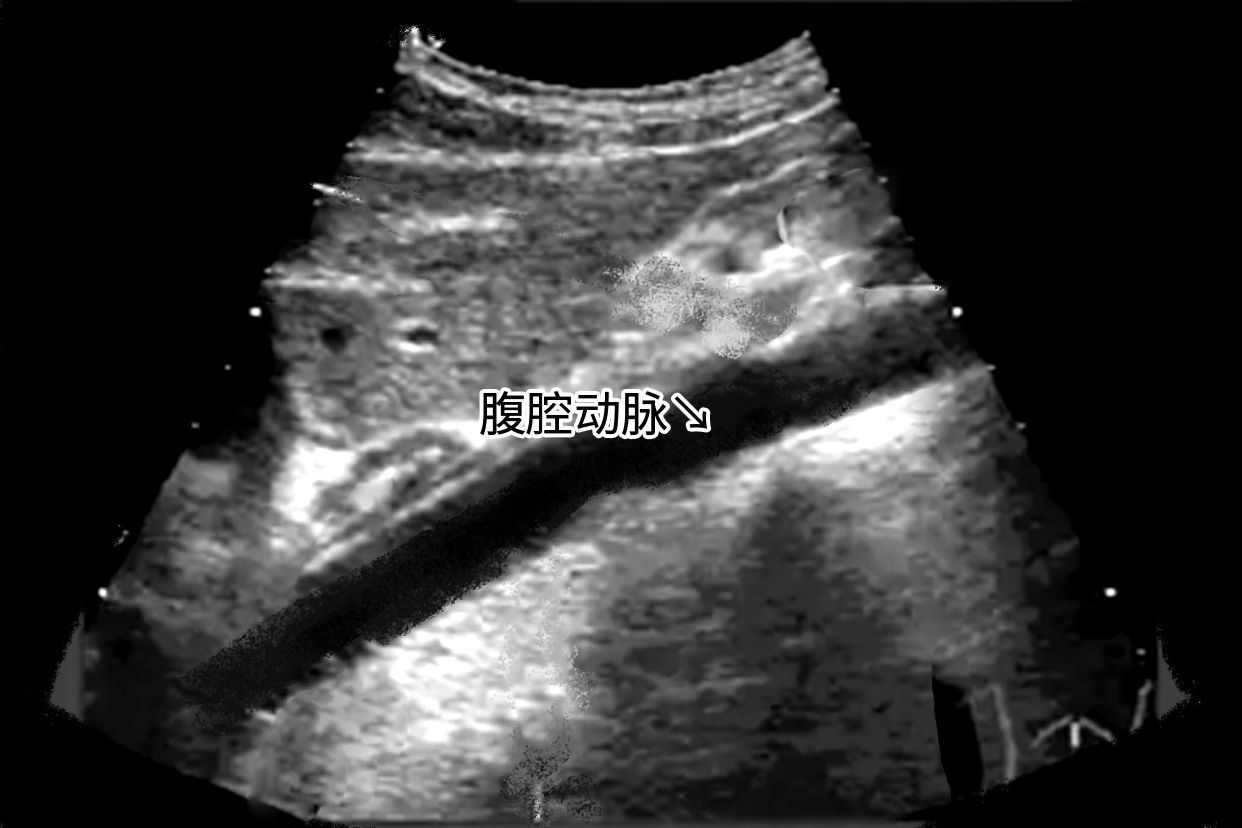

肝脏声像图改变是指在B超检查的过程中发现了肝脏的回声,肝内回声增粗、细密,静脉显示不清。患者需要做进一步的肝功能检查,才能了解病情的严重程度。

肝脏切面形态失常,肝脏各叶比例失调,常见左肝增大、尾状叶增大、右肝缩小等。肝包膜不光滑,高低不平,呈波浪状或锯齿状,肝内回声增粗、增强。